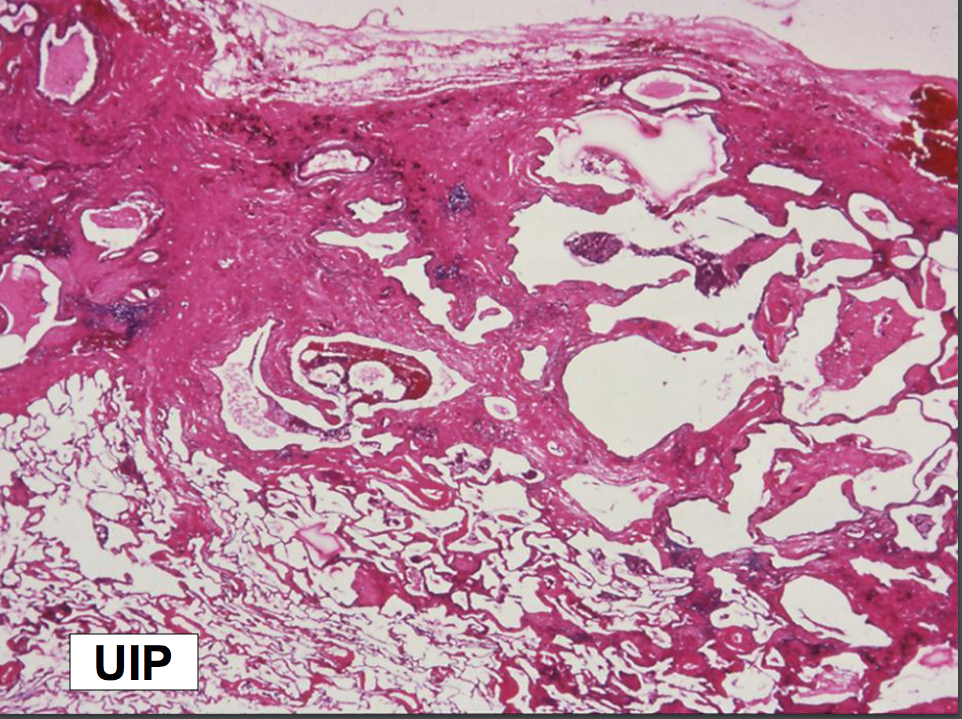

Gross pathology and the UIP pattern:

Microscopic Features of the UIP Pattern

*NOTE: Although IPF is characterized pathologically by the presence of fibrosis in a UIP pattern, this UIP pattern can also be seen in other nonidiopathic conditions. IPF by definition is idiopathic; if UIP is observed, a clinical diagnosis of IPF is only made after excluding other known causes of a UIP pattern!